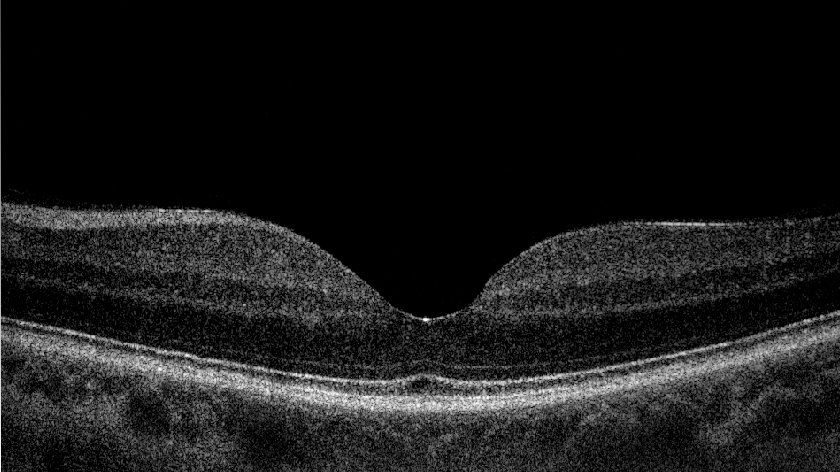

La tecnica trova largo uso in oftalmologia e ha numerose altre applicazioni biomediche. L'OCT sfrutta un raggio laser infrarosso analogamente a quello che fa un sonar con i fondali (a livello acustico), e riesce a ricostruire al computer la struttura Retinica, del Nervo Ottico e della Cornea, in due o tre dimensioni.

Consente, ad esempio, lo studio in sezione della Retina (Fig. 1a.b) e la diagnosi di eventuali patologie come DMS umida, Foro Maculare, Pucker Maculare, Edema diabetico e Edema infiammatorio, lo studio del nervo ottico e delle fibre nervose e quindi permette di fare una diagnosi precoce di glaucoma e di seguire poi l’evoluzione della patologia nel tempo.